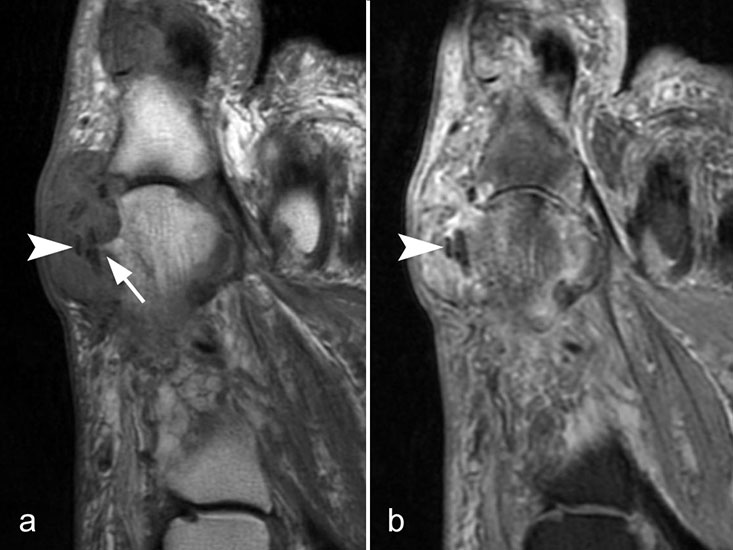

Typische Gichtmanifestation an der Großzehe mit Tophusstachel (Pfeil) und großem Tophus, in welchem Uratablagerungen identifiziert werden können (Pfeilspitze). T1-gewichtete Sequenz vor (a) und nach (b) Kontrastmittelgabe, letztere mit Fettsuppression.

Abbildung 15

Dies erst recht, wenn diese Arthritis am Großzehen­grundgelenk auftritt (Abb. 15). In diesen Fällen sollte man den Verdacht auch dann aufrechterhalten, wenn die MRT nur eine unspezifische Entzündung zeigt und die Harnsäurewerte, die starken Schwankungen unterliegen können, nicht erhöht sind.

Spezifische MR Befunde finden sich erst bei der chronischen Gicht, wenn sich in T2 sehr signalarme Kristallablagerungen und Gicht-Tophi bilden. Letztere führen dann häufig zu den aus der Röntgendiagnostik bekannten gelenkfernen Erosionen.

Abbildung 15: Typische Gichtmanifestation an der Großzehe mit Tophusstachel (Pfeil) und großem Tophus, in welchem Uratablagerungen identifiziert werden können (Pfeilspitze). T1-gewichtete Sequenz vor (a) und nach (b) Kontrastmittelgabe, letztere mit Fettsuppression.